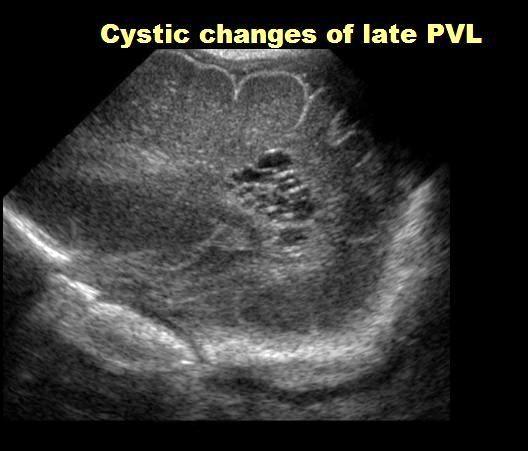

Classic PVL 22-32 weeks

Classic PVL

Acute to Chronic PVL on MRI (often at Term)

White Matter Injury of Prematurity

 Acute 2-4 days

 WM T2 Hyperintensity

 Foci of focal T1 shortening, not hemorrhage

White Matter Injury of Prematurity = PVL

Flare/PVL at 28 weeks

Term Equivalent Late changes